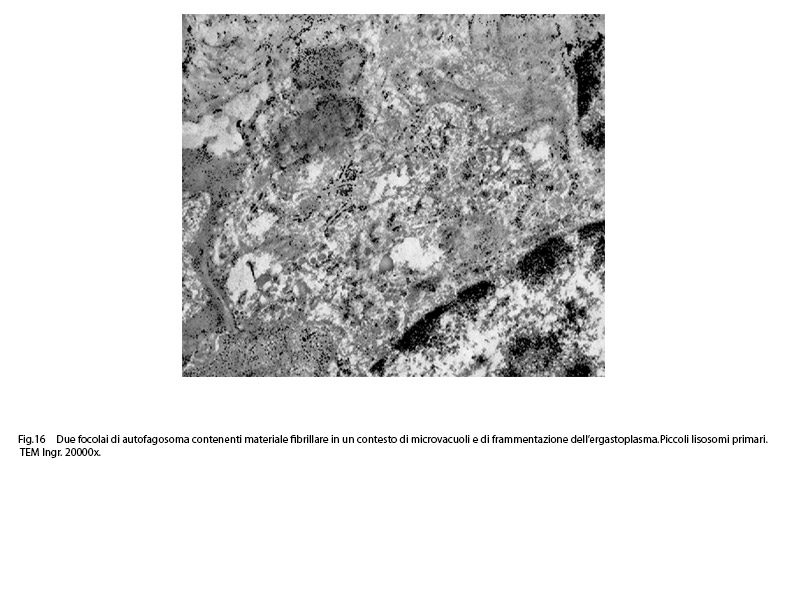

Fig.16  Fig.17